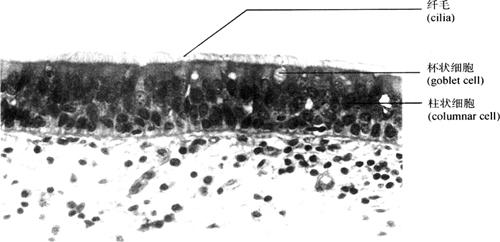

4.假复层纤毛柱状上皮(pseudostratified columnar epithelium) 由锥体形、梭形和柱状细胞组成。细胞的基部都位于同一基膜上,由于核不在同一水平面上,外观似多层,故称假复层。游离面有纤毛,细胞间夹有杯状细胞,可分泌黏液(图2-10)。主要分布于呼吸道腔面,纤毛可节律性摆动,将呼吸道内含灰尘、细菌等异物的黏液推向咽部,起到清洁保护作用。男性生殖系统副睾、输精管亦见此种上皮。

图2-10 假复层纤毛柱状上皮(400×)